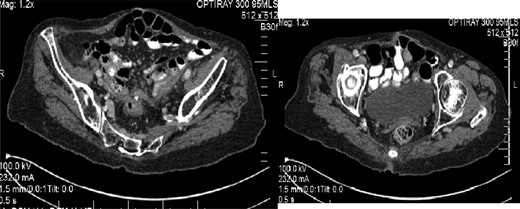

A CT angiogram was arranged which identified a large false aneurysm of the left internal iliac artery (Fig. 1) with probable communication to the rectal stump and the left ureter. The patient was transferred to the local vascular centre for endovascular coiling, which was successful.